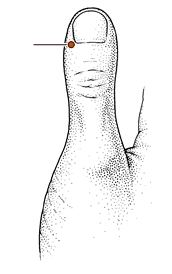

少商穴

经穴名。出《灵枢·本输》。别名鬼信。属手太阴肺经。井(木)穴。在手拇指末节桡侧,距指甲角0.1寸。布有来自前臂外侧皮神经和桡神经浅支的混合支,正中神经的指掌侧固有神经形成的末梢神经网和指掌侧固有动、静脉形成的动、静脉网。主治发热,昏迷,咳嗽,咽喉肿痛,癫狂,鼻衄等。斜刺0.1-0.2寸,或点刺出血。艾炷灸3-5壮;或艾条灸5-10分钟。